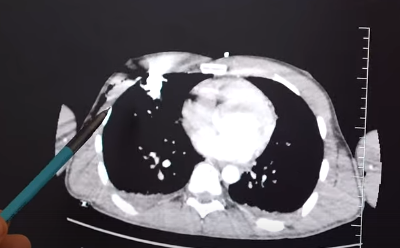

Специалистам Института Склифосовского предстояло извлечь 60-сантиметровый железный стержень из тела 23-летнего пациента.

Молодой человек оказался везунчиком - инородное тело, несмотря на размер, не задело жизненно важные органы.

Арматура незначительно повредила лёгкое и прошла через мягкие ткани. Тем не менее, находилась в опасной зоне, где расположены сердце и крупные сосуды.